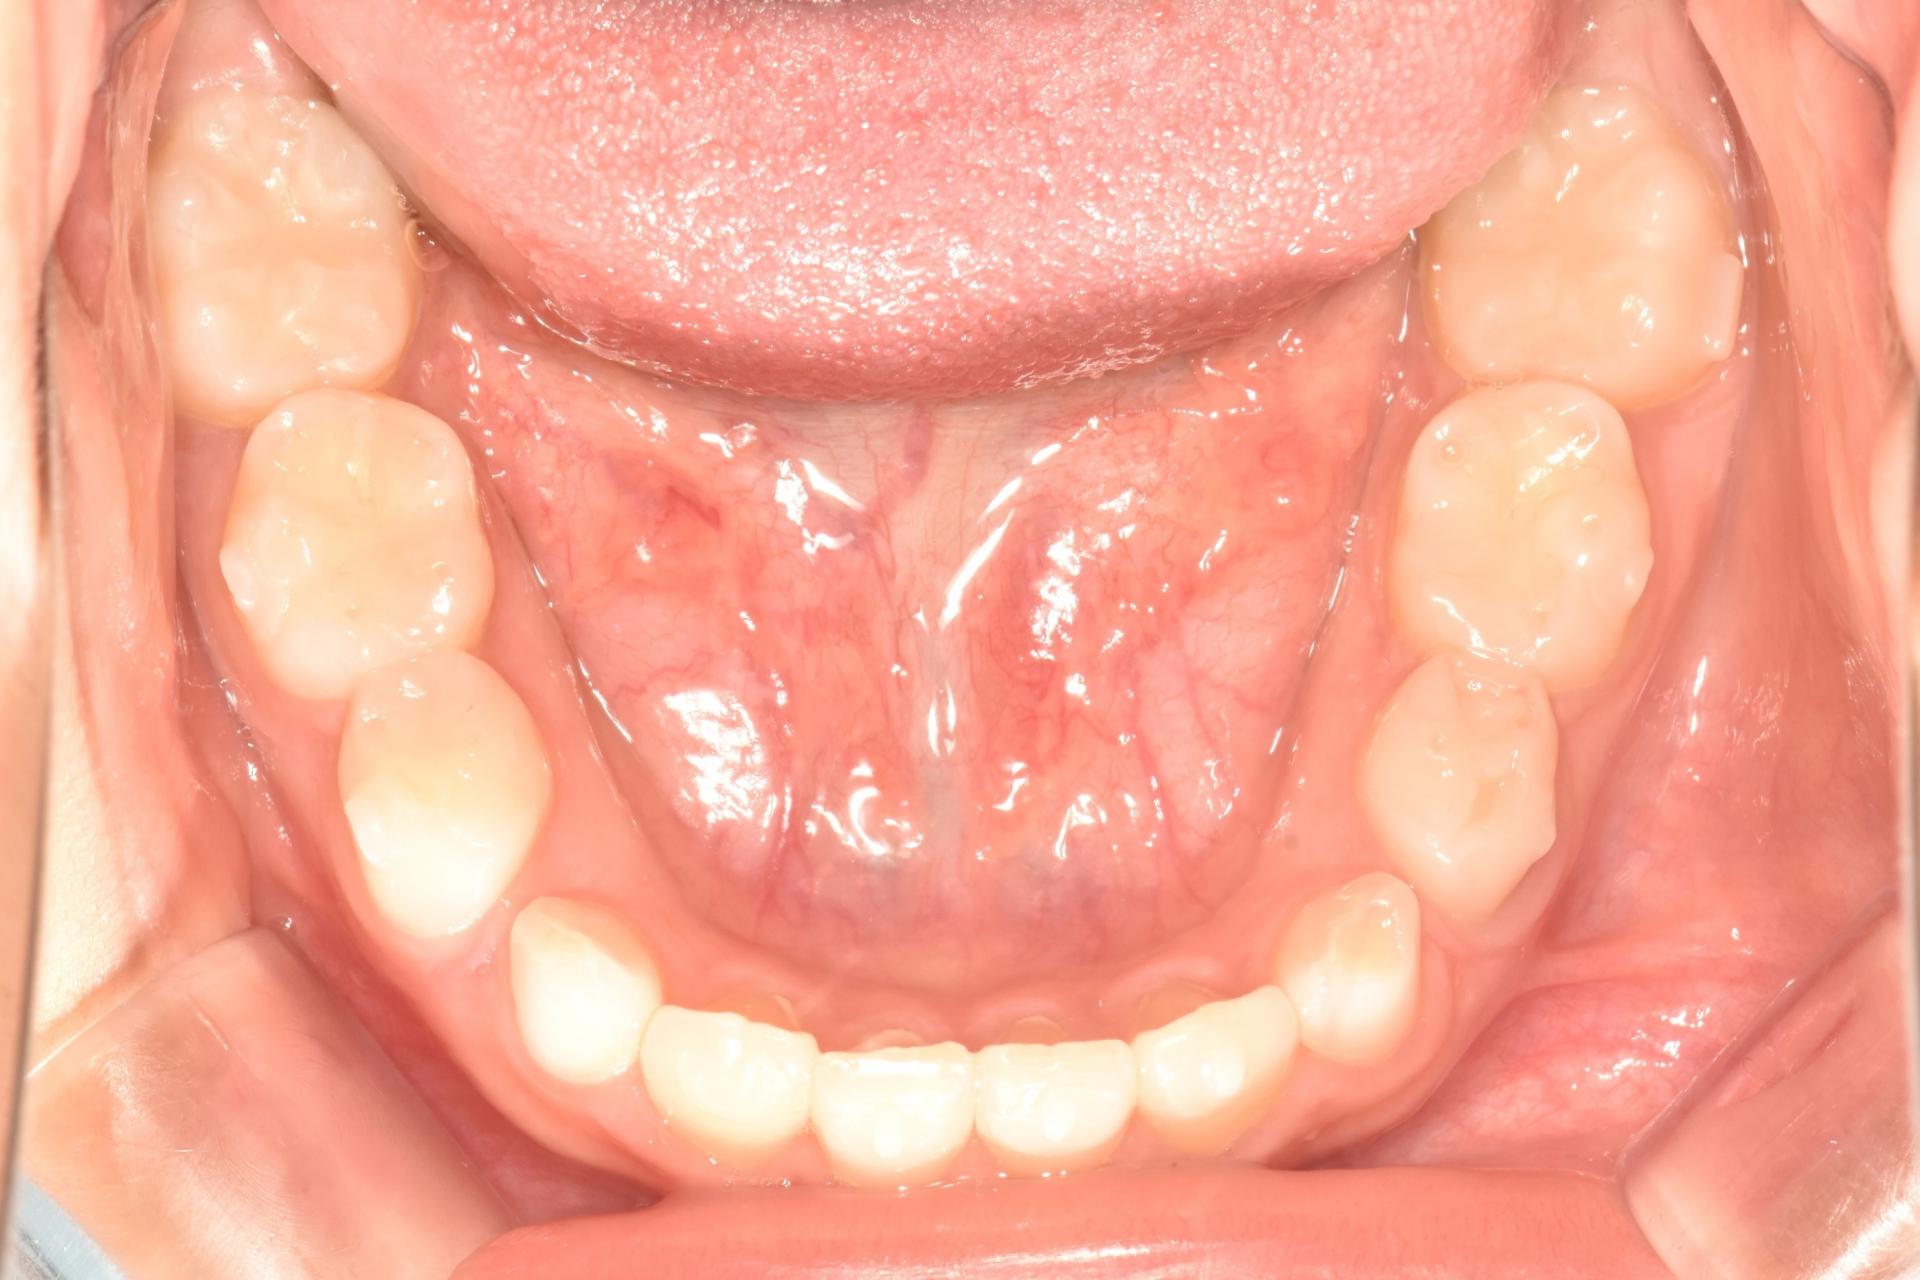

단 것 좋아하는 둘째 아이의 경우도 마찬가지로 수면치료 했습니다.

앞니, 어금니 모두 레진치료 했네요...^^;;

둘째 아이도 겁이 많은 아이지만 치과에 안좋은 기억이 전혀 없으며 이제는 초등학생이 되어 예쁜 영구치앞니로 모두 교환했습니다.

치료는 수면치료 하에 모두 마치고 이제 교정중인 둘째입니다.